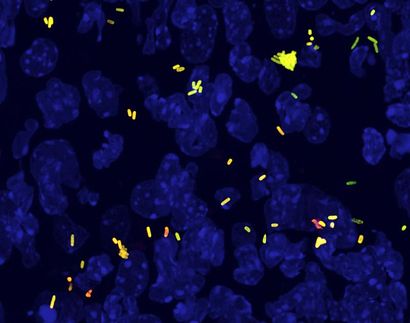

This image shows Streptococcus pneumoniae with black carbon.

The research focused on two human pathogens, Staphylococcus aureus and Streptococcus pneumoniae, which are both major causes of respiratory diseases and exhibit high levels of resistance to antibiotics.

The research team found that black carbon alters the antibiotic tolerance of Staphylococcus aureus communities and importantly increases the resistance of communities of Streptococcus pneumoniae to penicillin, the front line treatment of bacterial pneumonia.

Furthermore, it was found that black carbon caused Streptococcus pneumoniae to spread from the nose to the lower respiratory tract, which is a key step in development of disease.